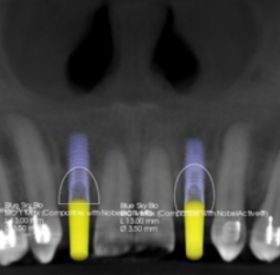

Step 1: Pre-surgical 3D planning.

Step 2: Pre-prosthetic 3D planning.